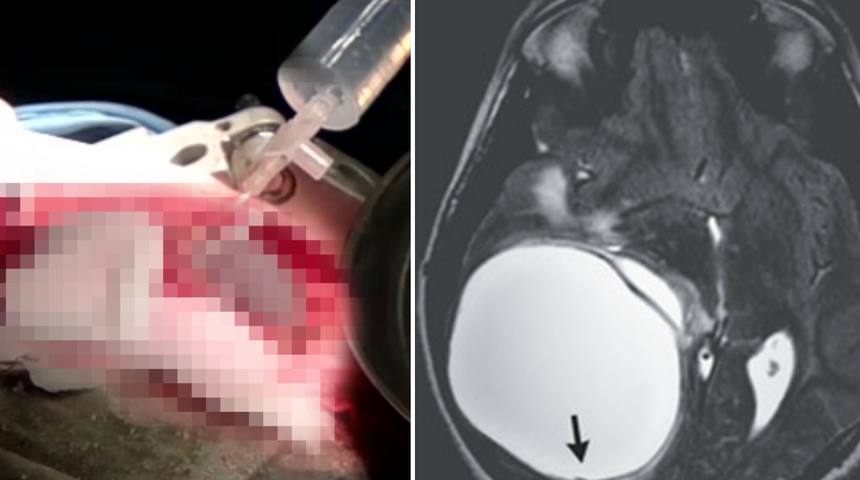

Hastanede yapılan MRI taramasında çocuğun beyninde büyük bir kist olduğu görüldü. Testlerden sonra, tenyaların neden olduğu bulaşıcı bir hastalık olan bir tür ekinokokkoz teşhisi kondu.

Kafatasında küçük bir deliğin kesilerek beyni ortaya çıkardığı bir kraniyotomi geçirdikten sonra, büyük kist başarıyla çıkarıldı. Video görüntüleri, doktorların yırtılmayı önlemek için kist duvarını beyinden nazikçe ayırdığını gösteriyor. Yerel raporlara göre, çocuk taburcu olduktan iki hafta sonra okula döndü ve normal faaliyetlerine devam etti. Ancak bu durum tedavi edilmediği takdirde durum ölümcül olabilirdi.